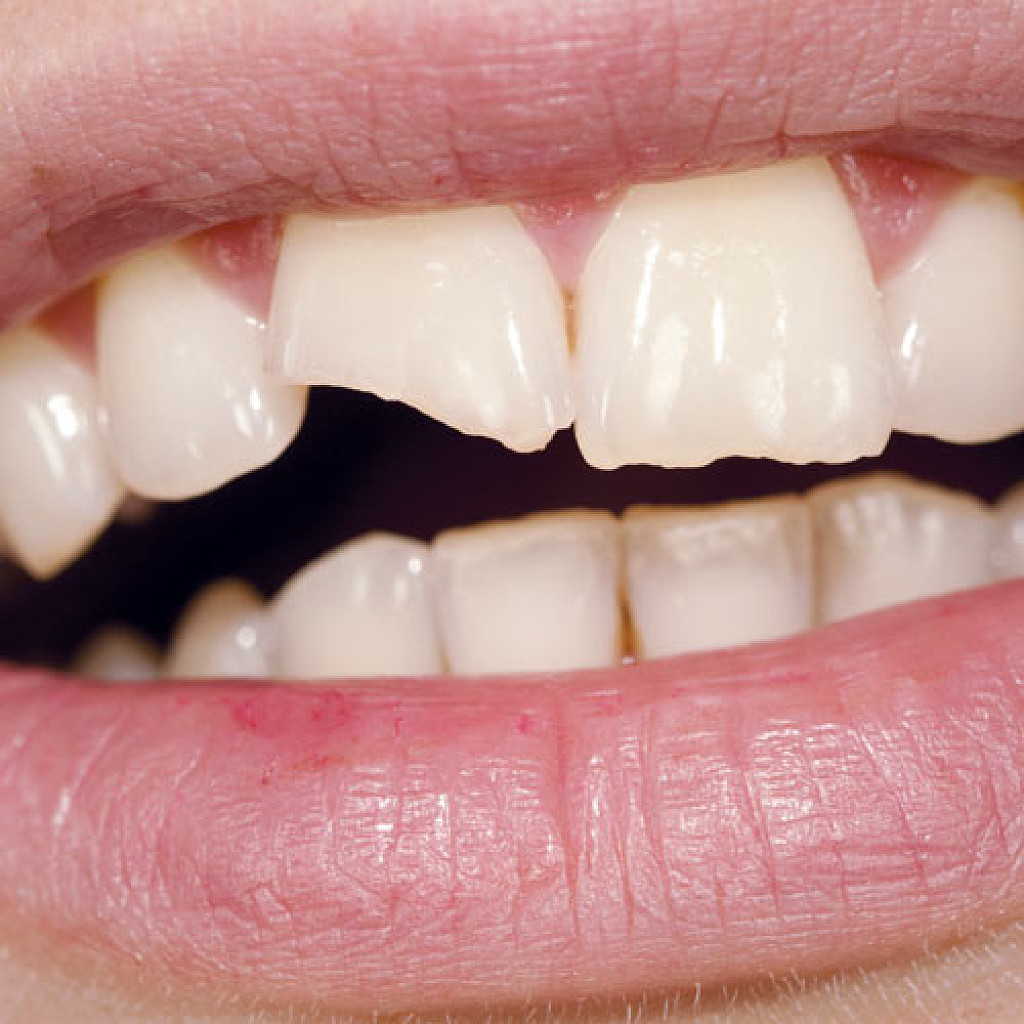

Will my chipped tooth go black?

If the chip in your tooth is just in the enamel (the hard outer layer of your tooth) then, so long as you keep the tooth clean, the chances are it will not go black. There is no need to see a dentist urgently, simply make an appointment at your earliest convenience to discuss how this can be repaired.

If the chip in your tooth goes through the enamel and into the dentine (the softer part of your tooth) then the dentine may pick up stains more readily and go dark. Because the dentine is softer, it will also be more prone to dental decay causing a black tooth. You should see a dentist about this; however, it would not be considered an emergency appointment unless it is accompanied by pain.

If the chip goes all the way through the enamel, dentine and down to the pulp (the living blood supply part of your tooth) this will more than likely be extremely painful and you may even see blood from the chip. If this is left untreated, not only could you be in extreme pain but the tooth could begin to die and will almost certainly go black. You will need to see an emergency dentist as soon as possible.

Can a Tooth Cracked In Half Be Fixed?

One moment you’re biting into a crisp, flatbread pizza, and the next, you’ve got a tooth cracked in half. There are a few reasons why this can happen with no warning, but luckily, your dentist can usually fix a cracked tooth. There’s plenty to know about what causes a tooth to crack, and what you can do about it before it’s beyond restoration.

Reasons a Tooth Might Break

Over time, jaw clenching, teeth-grinding and crunching hard objects like candy or ice can damage your tooth enamel and cause the tooth itself to crack. The pulp inside your tooth contains nerves and blood vessels and, according to the American Association of Endodontists (AAE), can therefore become painful if the tooth has suffered a crack in it. A telltale sign of a cracked tooth is sudden pain while eating, especially if your food is an extreme temperature, though it is possible to have a cracked tooth and not feel it.

What to Do if a Tooth Cracks in Half

Call your dentist’s office for an appointment right away to let them know your tooth cracked in half. A broken tooth is not something you should put off, because the longer you wait, the more you risk infection in the tooth’s pulp – which can spread to the gum and bone beneath your tooth. If you can’t see your dentist immediately, follow your usual oral hygiene routine up until your scheduled visit, but use extra care.

How to Repair a Cracked Tooth

Your dentist will then be able to take a look at the damage and decide the best treatment for saving your tooth. Ultimately, however, treating a cracked tooth depends on how extensive the fracture is. If a tiny piece of enamel or filling has chipped off, you may only need a new filling or some bonding material to restore the chipped portion. Part of your tooth may also be salvaged if only a small piece broke off, allowing your dentist to place a crown over it to protect the remainder of the tooth. Or, endodontic surgery may be required to remove the fractured portion. Other times, the crack may extend down into the pulp, and a root canal or tooth extraction may be more appropriate.

Taking swift action can make a big difference in your ability to save a cracked tooth, so be sure to get on your emergency dentist appointment soon. It could prove vital in preventing the loss of the tooth altogether.